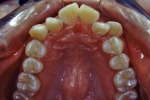

日本矯正歯科学会専門医課題症例(第3症例)

カテゴリー:Class Ⅱ division 1(抜歯症例)

| 初診時